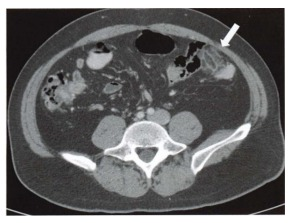

Mulher de 29 anos inicia com dor abdominal aguda em flanco esquerdo. O sintoma é bem localizado e a paciente consegue apontar o local exato da dor. Realizada tomografia com contraste endovenoso que evidencia densificação focal da gordura pericolônica esquerda, na borda antimesentérica, com aspecto em “dedo de luva”, apontado pela seta na figura abaixo. Assinale a alternativa com o diagnóstico CORRETO:

Enunciado 3505924-1